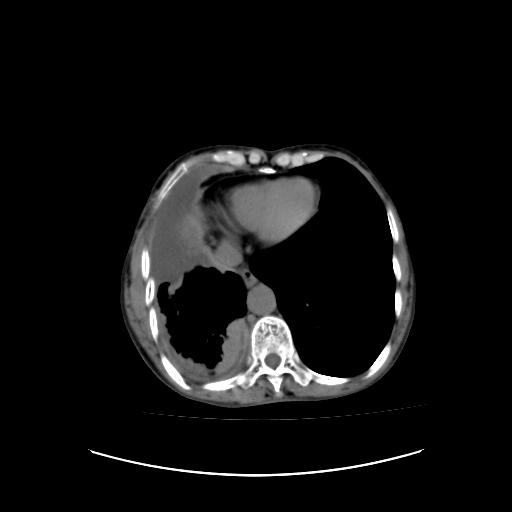

标题: CT16930:女 59 胸痛6个月 胸水脱落细胞学见瘤细胞 [打印本页]

标题: CT16930:女 59 胸痛6个月 胸水脱落细胞学见瘤细胞

右侧胸膜增厚,局部呈结节状增厚,右侧胸腔少量积液。双肺未见确切肿块影。纵隔未见淋巴结肿大。气管、支气管通畅。考虑右侧胸膜间皮瘤(恶性?)可能性大。不除外癌性胸膜炎。

右侧胸廓塌陷,右侧胸膜广泛增厚并见多发胸膜结节,右侧少量胸腔积液并包裹。

胸膜转移瘤  包裹性胸腔积液  肺内转移

右胸腔结节均考虑来自胸膜(部分来源于叶裂),考虑胸膜间皮瘤或转移瘤.